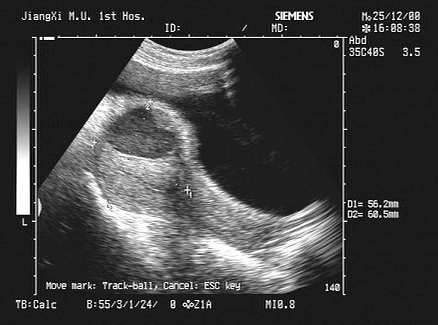

10、单项选择题

女,40岁,有时右上腹隐痛2年余。结合超声声像图,最可能的诊断为()

A.肝血管瘤

B.肝脓肿

C.小肝癌

D.转移性肝癌

E.肝囊肿